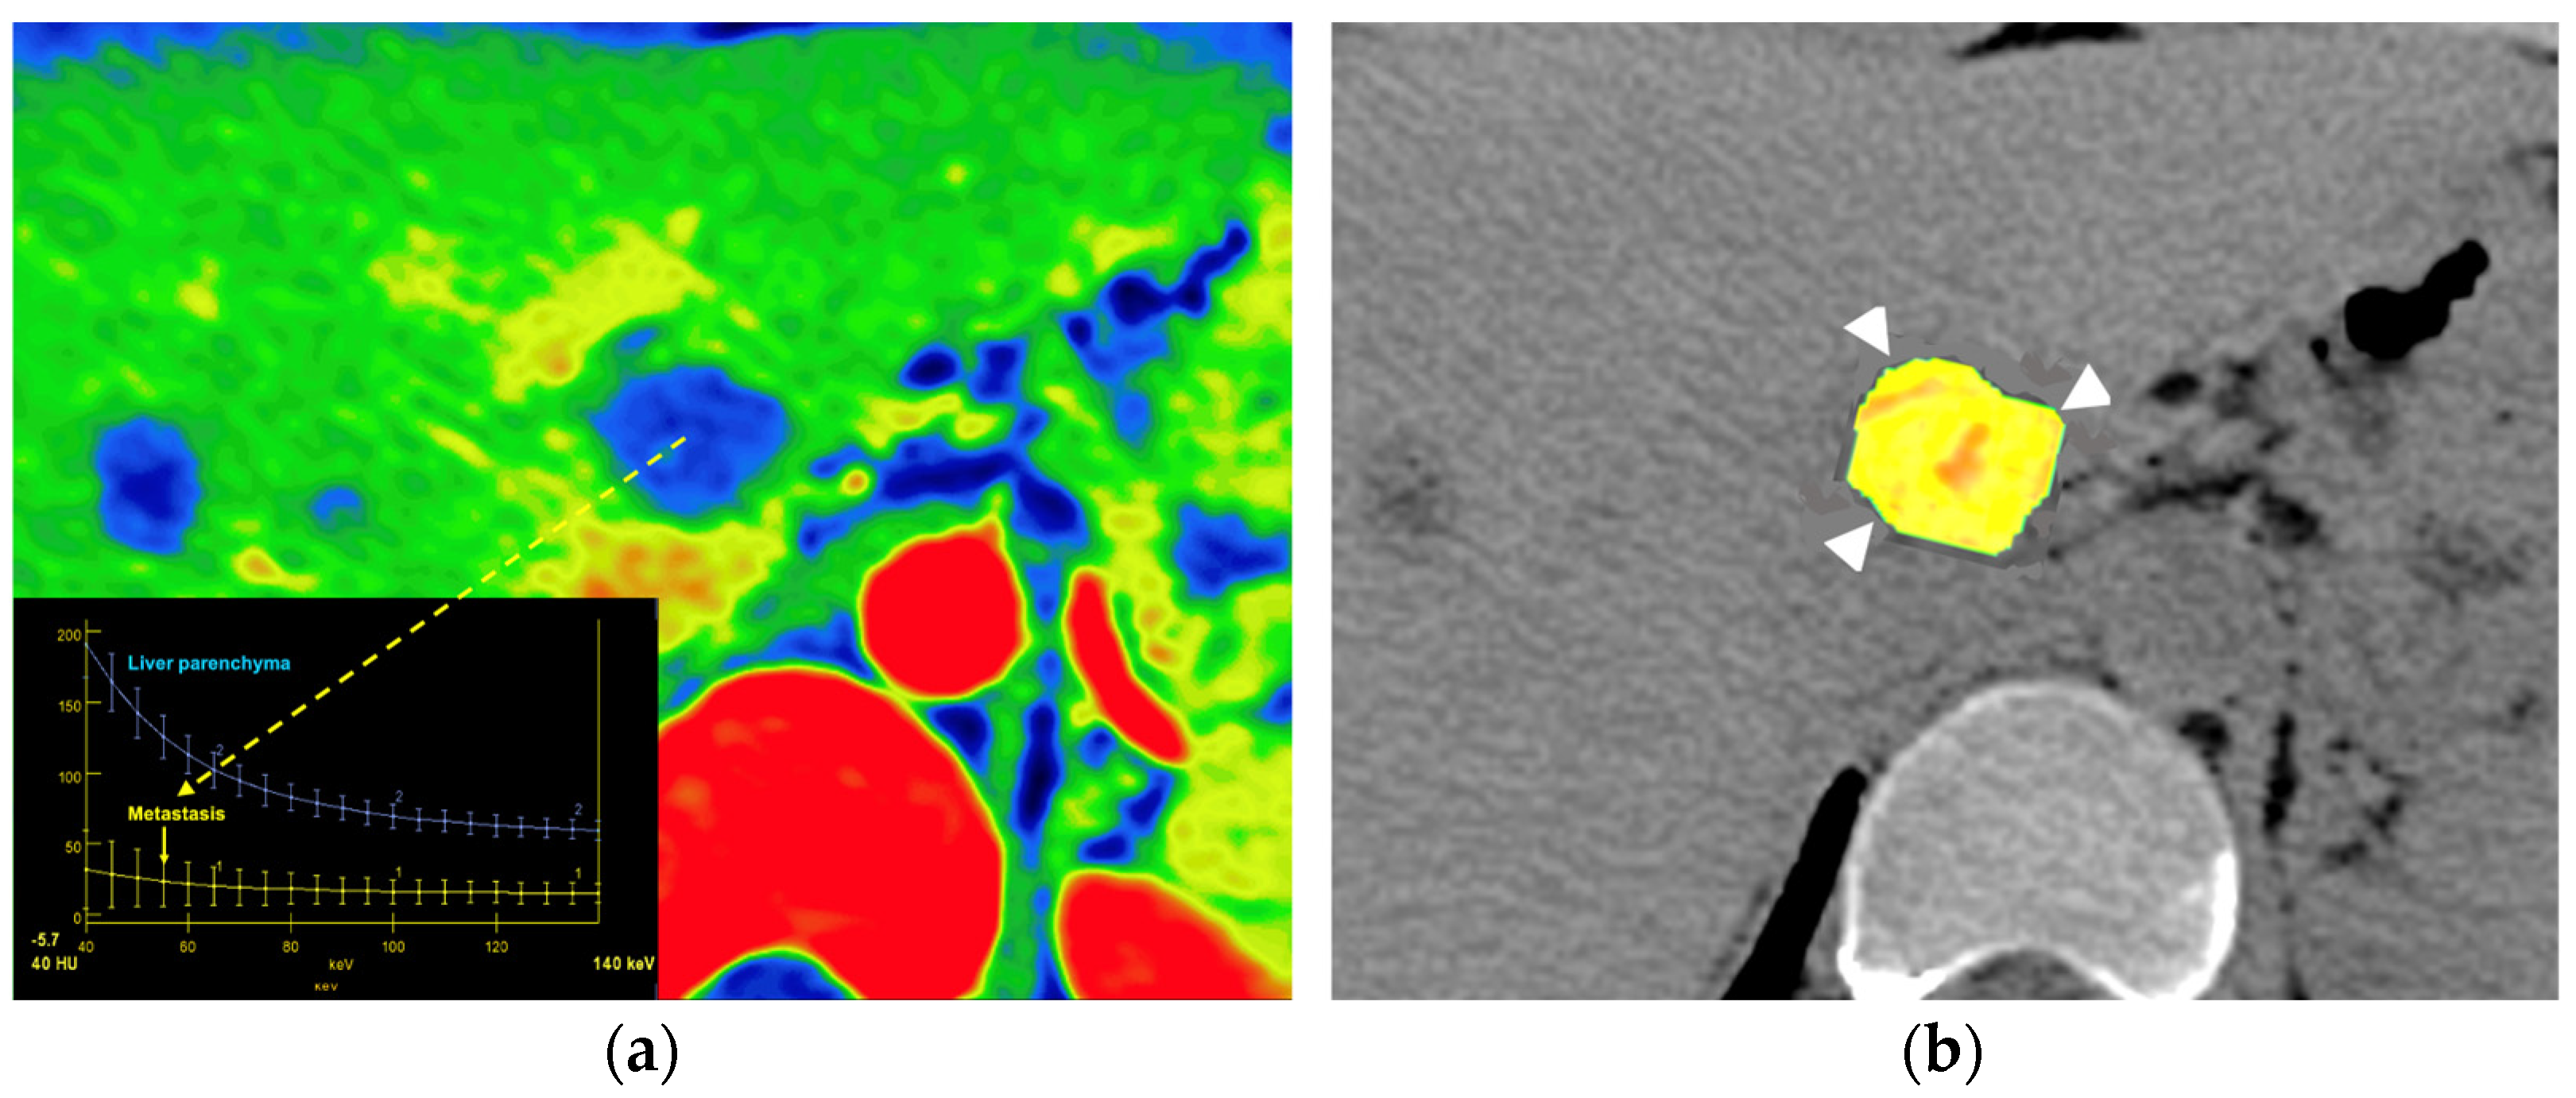

- Iodine concentration may be a surrogate marker of changes in tumor perfusion due to therapy [96]. Different iodine-related parameters have been proposed, such as concentration of intralesional iodine, vital iodine tumor burden, and (lesion volume × iodine concentration), which may be more sensitive than the evaluation criteria based on maximum diameter or change in CT value.

- Zeff is also a quantitative index for characterization of the composition of a voxel, although determining a biological correlation of these changes to tumor microenvironment is challenging.